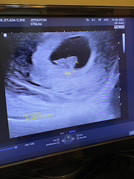

7w4d